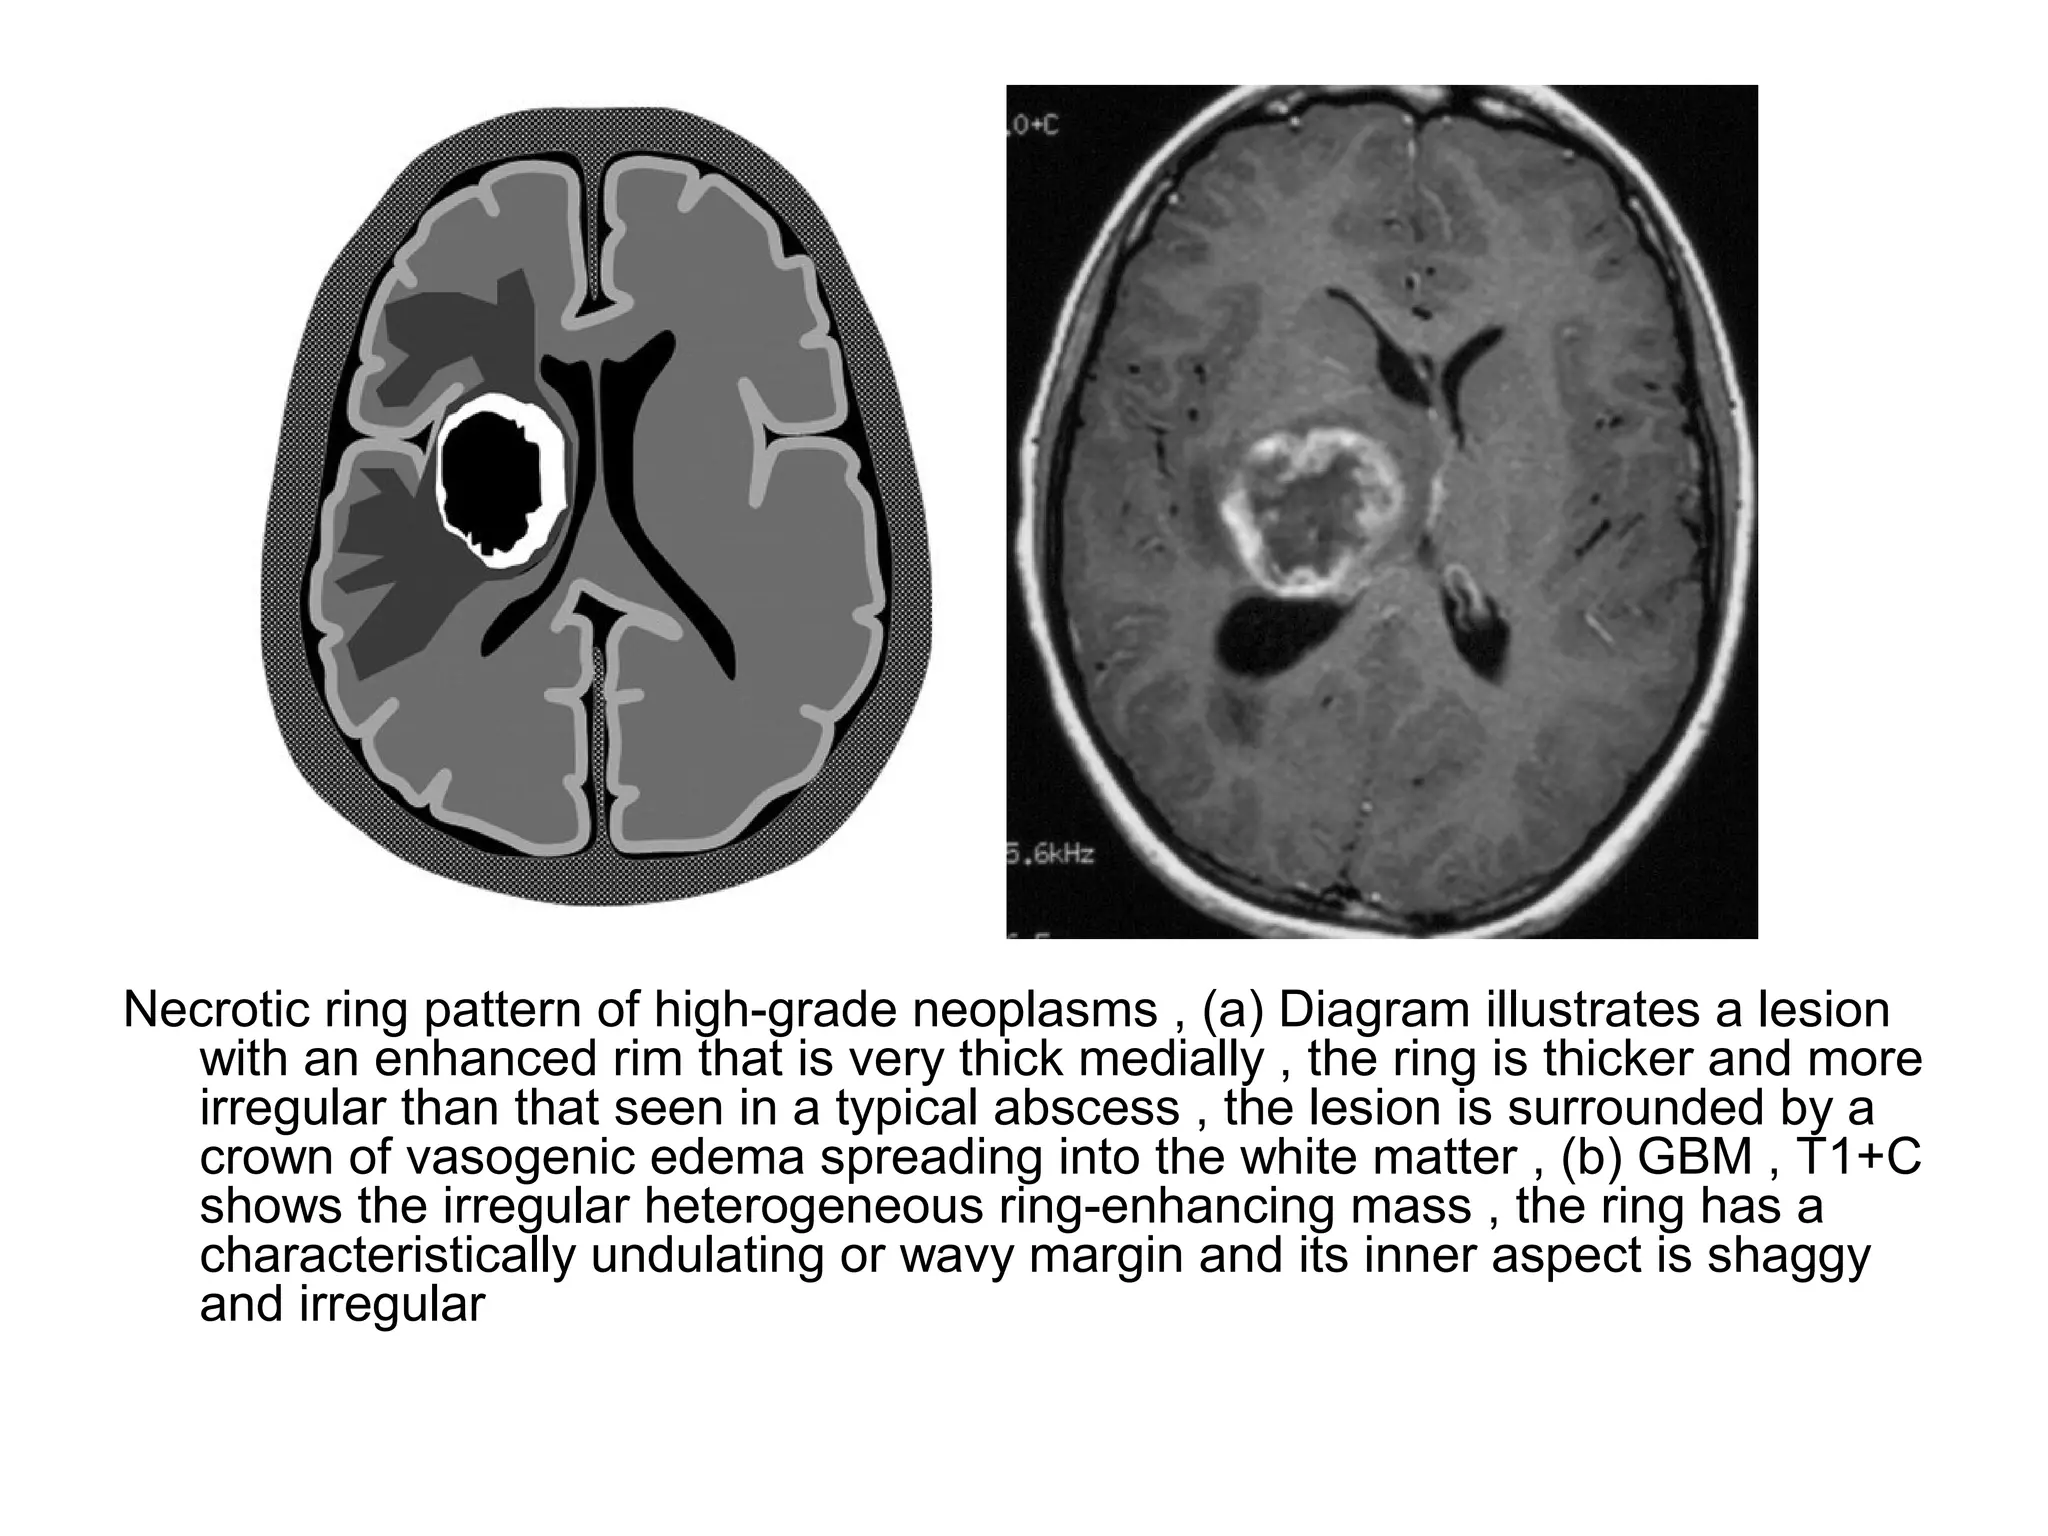

Necrotic ring pattern of high-grade neoplasms , (a) Diagram illustrates a lesion

with an enhanced rim that is very thick medially , the ring is thicker and more

irregular than that seen in a typical abscess , the lesion is surrounded by a

crown of vasogenic edema spreading into the white matter , (b) GBM , T1+C

shows the irregular heterogeneous ring-enhancing mass , the ring has a

characteristically undulating or wavy margin and its inner aspect is shaggy

and irregular